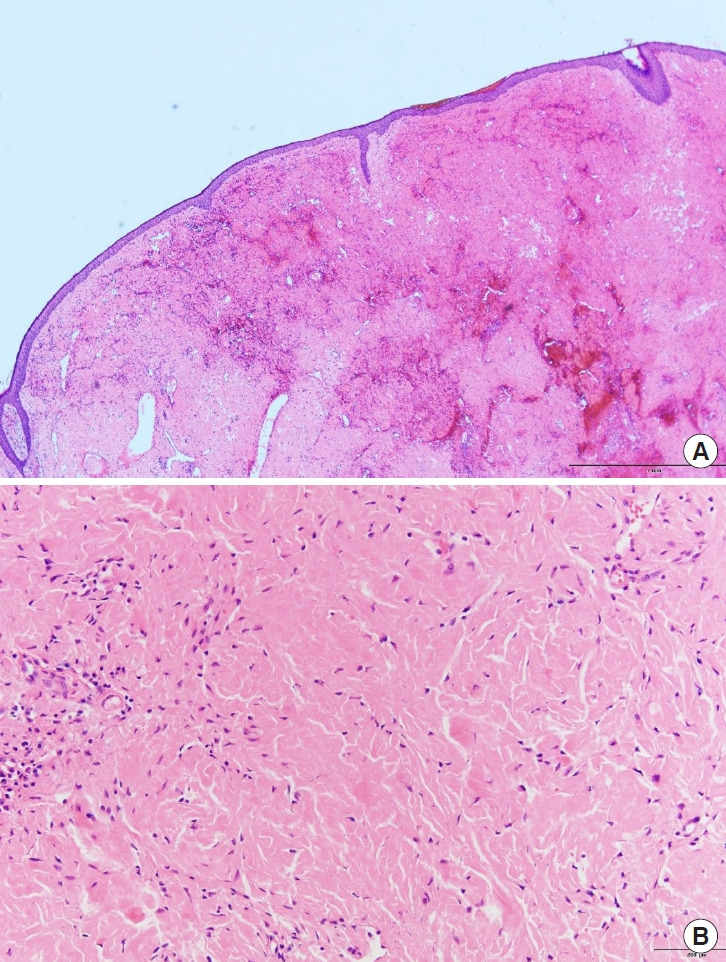

弹性纤维瘤是一种罕见的软组织肿瘤,最常见于肩胛下区域。在其他几个解剖位置也有报道。据我们所知,以前没有报道描述面部前部的弹性纤维瘤。一位36岁的智障男性被转介到我科评估中部无痛性多结节病变。该病变最初被皮肤科误诊为皮肤病,并进行了相应的治疗,但病情恶化,促使转介到我科。我们进行了手术切除病变和重建的皮肤缺损与皮肤移植。组织病理学检查证实为弹性纤维瘤。本病例强调了面部肿瘤鉴别诊断中包括弹性纤维瘤的重要性,特别是当表现为瘤状病变时。

Elastofibroma is a rare soft tissue tumor that most commonly occurs in the subscapular region. It has also been reported in several other anatomical locations. To our knowledge, no previous reports have described elastofibromas in the anterior aspect of the face. A 36-year-old man with intellectual disability was referred to our department for the evaluation of a painless multinodular lesion on the philtrum. The lesion was initially misdiagnosed as a dermatologic condition by the department of dermatology and was treated accordingly, however, it worsened, prompting referral to our department. We performed a surgical excision of the lesion and reconstructed the resulting skin defect with a skin graft. Histopathological examination confirmed the diagnosis of elastofibroma. This case underscores the importance of including elastofibroma in the differential diagnosis of facial neoplasms, particularly when the presentation is phymatous.